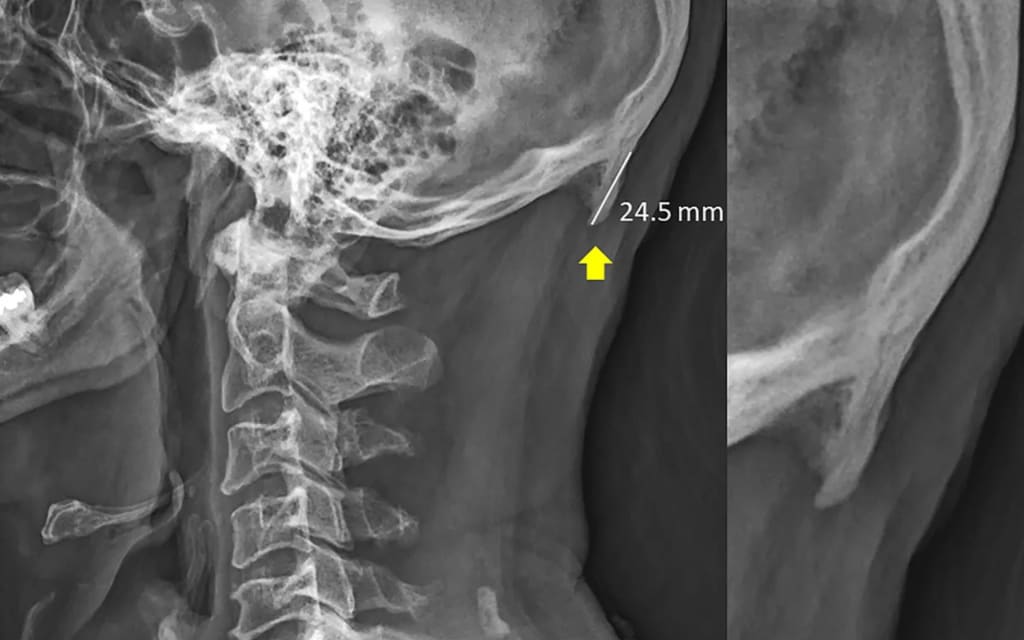

so how is it doing this it's all to do with something called an EOP or outside

occipital projection a few specialists and

commentators have been more colorful and

portrayed it as a froth ball or a friend

like a horn in reality the EOP may be a development

of bone found within the back of the cranium.

Shahar has sayers taken note that in youthful

individuals the EOP showed up to be more

far-reaching from this they hypothesized

that youthful people pose whereas

continually checking their phones and

tablets were a major figure in the screen

time the neck

impulses wrench forward the hypothesis

is that by extending forward additional

weight is put on the range where the shape

me muzzle to compensate the EOP gets

steadily longer developing to around

a few milliliters the impact has too

alluded to as content neck the funding